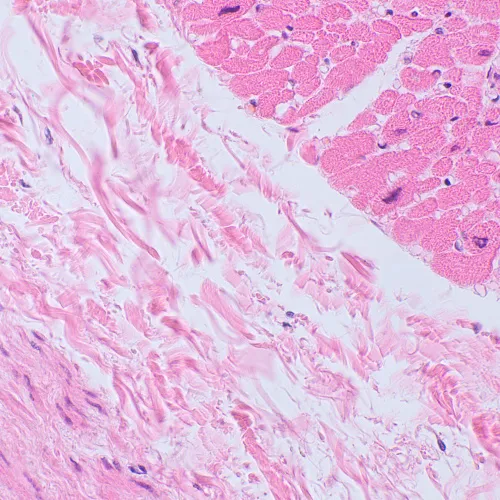

Il microscopio MAGUS Bio 250TL serve a esaminare campioni in sezioni sottili e strisci di materiali biologici. Le osservazioni sono effettuate con tecnica di microscopia in campo chiaro e in luce trasmessa. Una luce a LED da 3 watt fornisce l’illuminazione e le ottiche presentano obiettivi planacromatici corretti all’infinito. Questo microscopio prevede la possibilità di usare accessori aggiuntivi, compresi dispositivi per le osservazioni in campo oscuro, con luce polarizzata o contrasto di fase. Questo modello di microscopio è l’ideale per le analisi di laboratorio, la ricerca scientifica e l’insegnamento.